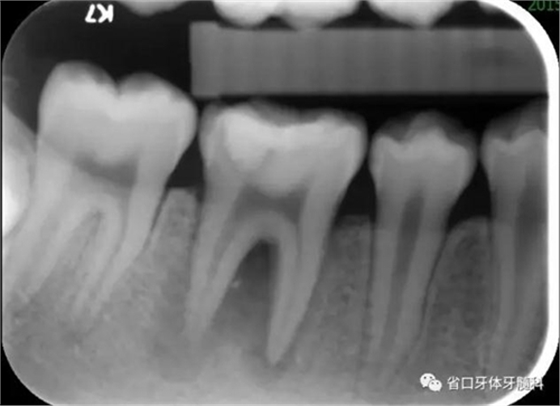

檢查:46牙合面牙色充填物,叩+,松I度,探及頰舌側根分叉處牙周袋深及根尖區(qū),頰側牙齦略腫脹。

圖1 初診X片示根尖周及根分叉大范圍低密度影像